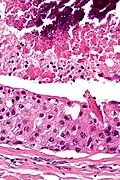

Their histologic appearance is similar to ductal breast carcinoma.

Very high mag.